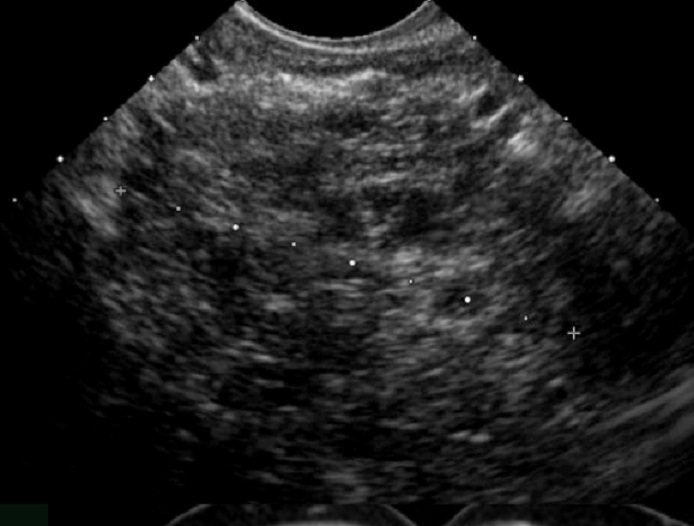

Echographie : Aspect

echographique lesionaire du cystadenome mucineuse du

pancreas est image du tumeur multiloculaire aechogen ou

hypoechogen , paroi epaisse > 2mm parfoi fin , a taille de

plus de > 10cm , forme par des petites kystes de moins < 2cm ,

parfois macrokystique , situe

dans le pancréas corporéo-caudal . N"a pas de

communication canalaire et lesion de calcification peripherique

parfois se en voyait